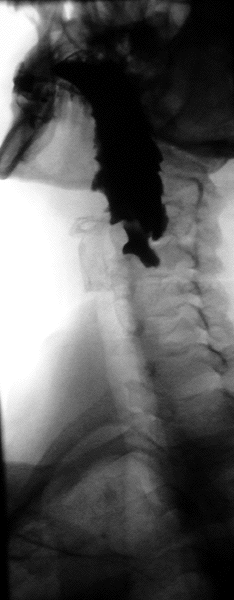

![]() Normal Barium swallow flouroscopic image, showing the ingested barium sulfate being induced down the oesophagus by peristalsis. | |